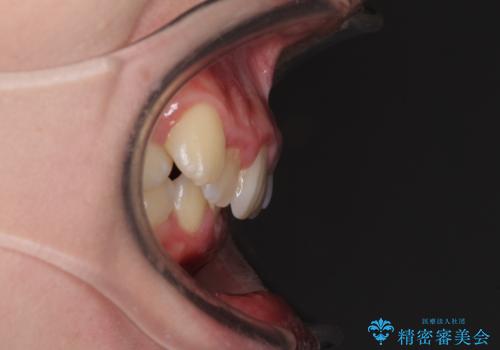

- 八重歯を気にして来院された患者様です。

八重歯の後ろの歯を1歯抜歯し、補助装置(リンガルアーチ)を用いて八重歯の位置を改善し、その後インビザラインにより矯正治療を行うこととしました。

下顎前歯が1本欠損したスリーインサイザーという状態であるため、上下の前歯の咬み込みが深くなったり、奥歯の咬み合わせが理想的なものとならなかったりという仕上がりになってしまいます。

前歯の見た目や奥歯の咬み合わせに、患者様が違和感を感じない状態として治療を終えました。